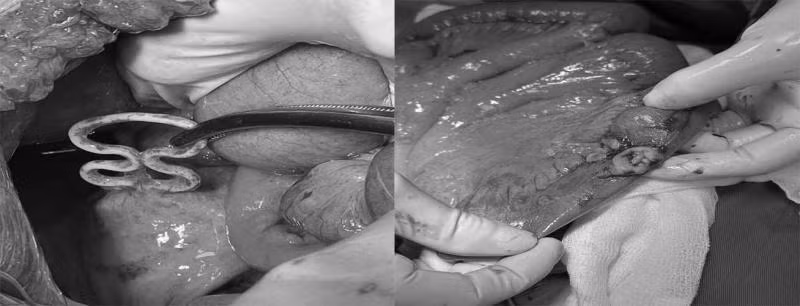

Các bác sĩ đã tiến hành lấy dụng cụ tử cung trên cơ tử cung, khâu phục hồi cơ tử cung, lỗ thủng ruột non, cầm máu, lau rửa và đặt dẫn lưu ổ bụng. Sau phẫu thuật 24h, sức khỏe bệnh nhân ổn định và được theo dõi sát quá trình hồi phục.

Bác sĩ CKI Nguyễn Thanh Hưng – Khoa Ngoại, Bệnh viện Bãi Cháy cho biết: "Bệnh nhân này do đặt vòng tránh thai nhiều năm, nhưng không kiểm tra nên không phát hiện được vòng đã ăn sâu vào cơ tử cung, xuyên qua cơ tử cung vào ổ bụng gây thủng ruột non, viêm phúc mạc".